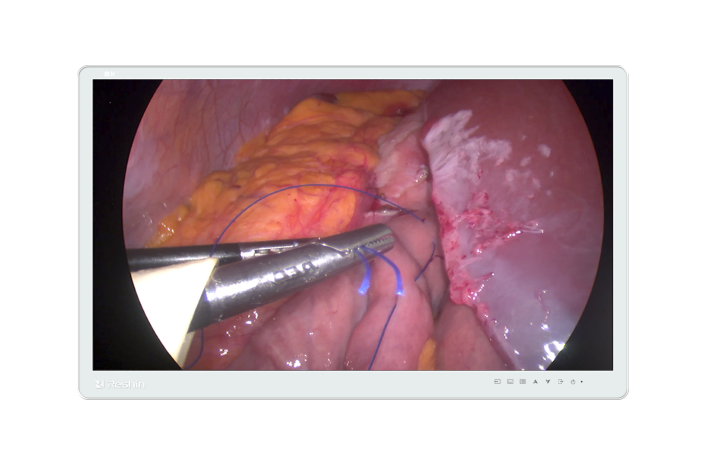

MS32YSAP

31.5英寸外科手術(shù)監(jiān)視器,擁有全球頂尖級(jí)8KQUHD超高分辨率,信息容量是4K UHD的4倍,畫質(zhì)更清晰細(xì)膩;顯示色彩占據(jù)自然界色彩比例高達(dá)50%,是傳統(tǒng)產(chǎn)品的1.5倍,更適合于高度色彩還原的手術(shù)領(lǐng)域;具備齊全的信號(hào)接口,適用于多種圖像顯示,且完全滿足手術(shù)室長(zhǎng)距離無干擾傳輸?shù)男枨蟆?/span>